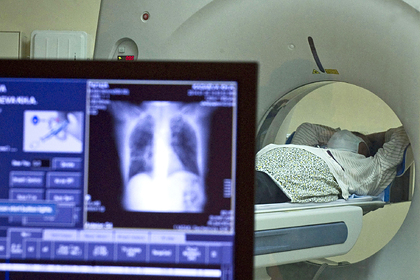

Курильщикам врачи советуют ежегодно делать компьютерную томографию грудной клетки, чтобы вовремя диагностировать рак легкого, трахеи и бронхов. Для выявления рака шейки матки женщинам старше 30 лет следует раз в год сдавать мазок на цитологию или проходить ПАП-тест. В случае с раком молочной железы начинать делать скрининг можно уже с 25 лет. В возрасте 25-30 лет врачи советуют женщинам делать УЗИ молочной железы, а после 35 лет — маммографию.